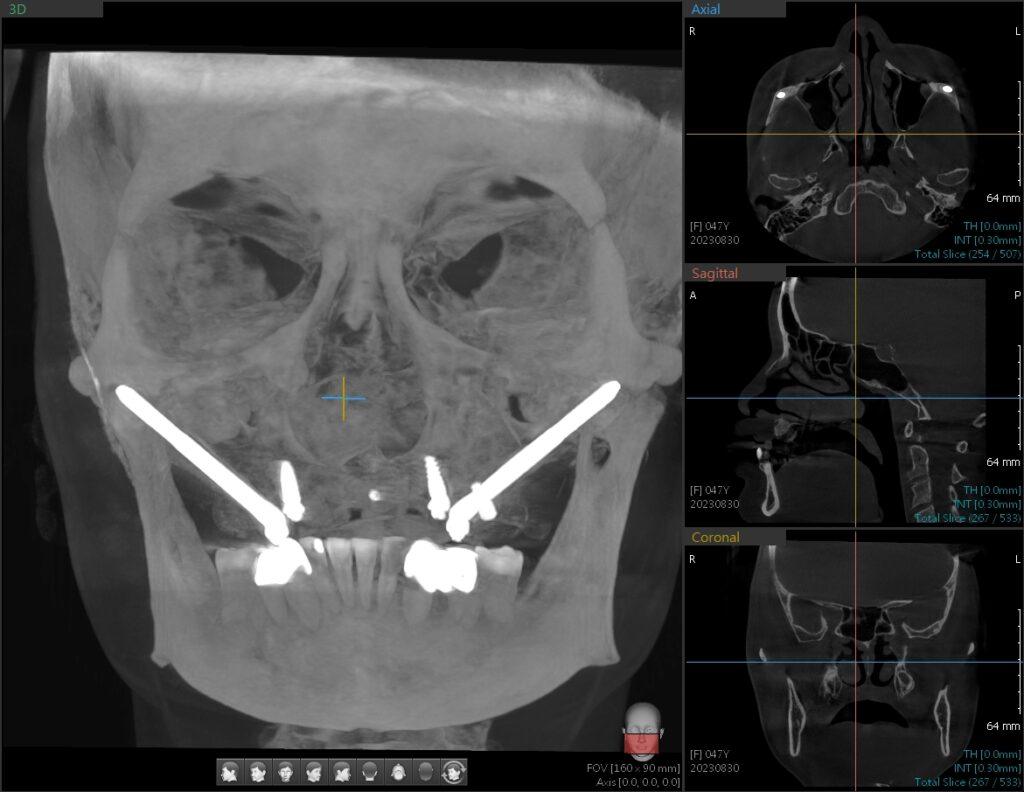

📸 CBCT 斷層掃描是關鍵。需判斷:

- 上顎前方是否還有足夠骨質?

- 顴骨高度、厚度與位置是否能安裝植體?

- 是否有鼻竇纖維化、過去手術疤痕等風險?

📍因此,請務必選擇有完整影像評估與顱顏解剖經驗的醫師,才能安全且精準完成這類手術。